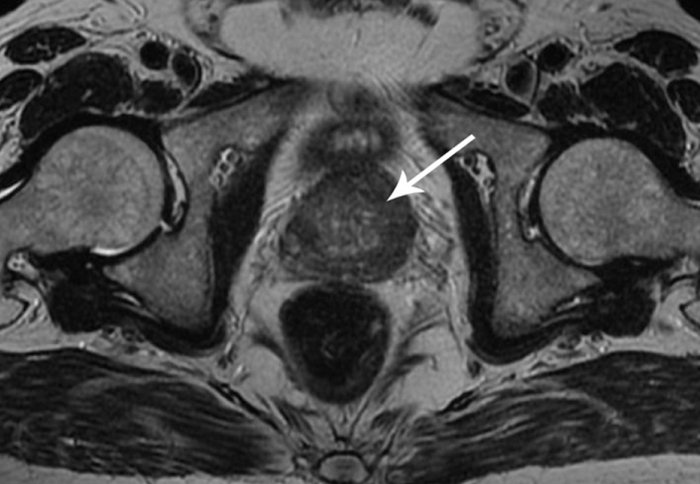

An MRI scan of prostate cancer

A new clinical study will test for the first time if MRI scans can be used for population screening to detect prostate cancer more accurately.